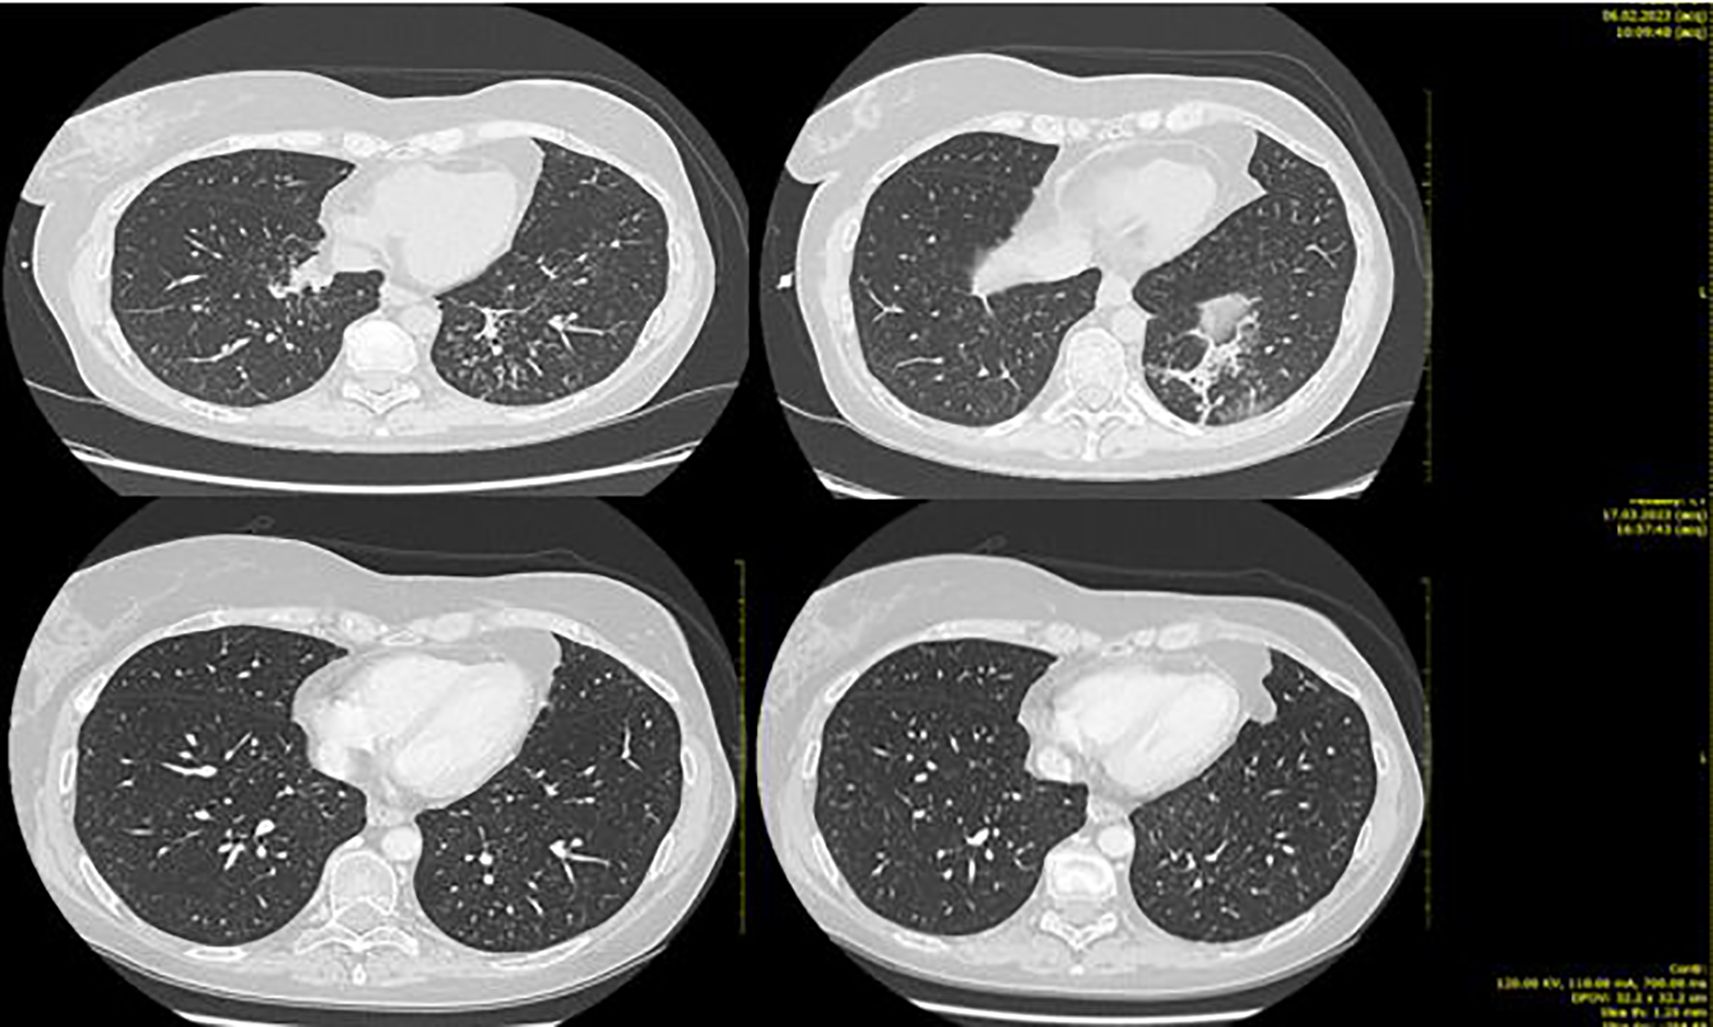

The fifth line with T-DXd treatment was administered from April 2021 to January 2023, with partial response at the first instrumental evaluation in June 2021 and complete response at the second one in September 2021 (Figure 3).